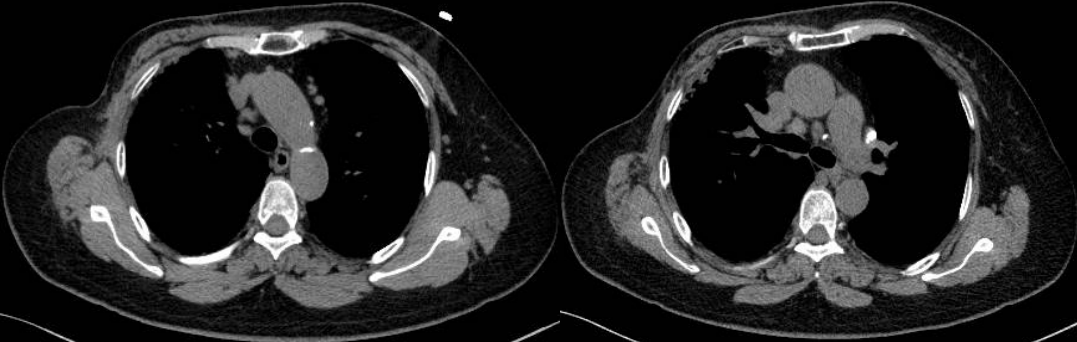

患者8個(gè)月后復(fù)查胸部CT示:縱隔、雙肺門(mén)淋巴結(jié)較前明顯縮小,較大者約1.4×1.1cm。

此例患者由于乳腺癌的病史,臨床初步懷疑轉(zhuǎn)移。PET/CT顯示縱隔、肺門(mén)淋巴結(jié)腫大,且呈對(duì)稱(chēng)性分布,密度均勻,邊界清晰,無(wú)明顯融合,F(xiàn)DG高攝??;此外可見(jiàn)多發(fā)腹盆部,頸部淋巴結(jié)次之,分布較散,體積及FDG攝取小于縱隔和肺門(mén)淋巴結(jié),也不是乳腺癌術(shù)后易轉(zhuǎn)移的部位。綜上考慮符合結(jié)節(jié)病表現(xiàn),最終得到病理證實(shí),患者因此避免了不必要的抗腫瘤治療。